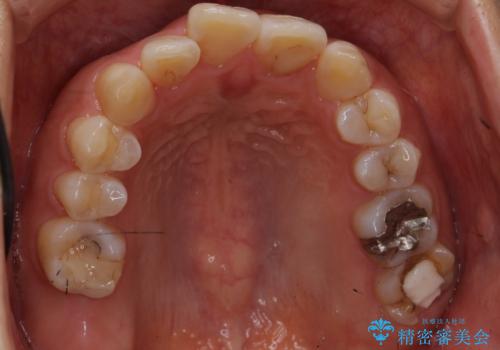

銀歯も白くということでしたので虫歯治療も一緒に行っています。

左上7の根の治療や左下56銀歯の治療なども行いました。

右下7は根管治療をおすすめしましたが、患者様のご希望により抜歯となり、そのスペースを利用して下の前歯をならべています。